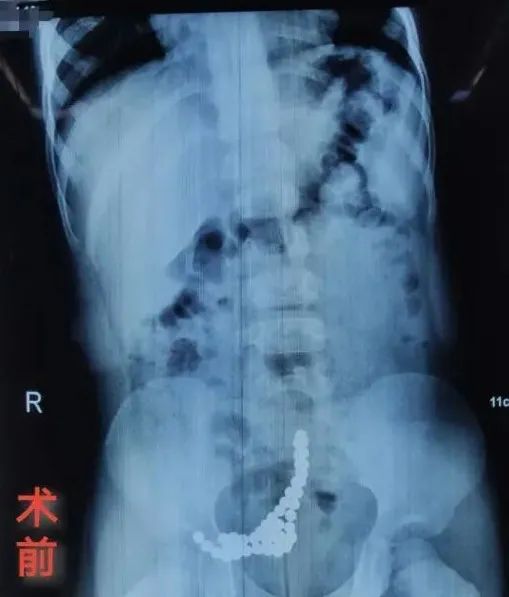

前阵子,西安一名3岁的小男孩因腹痛急诊入院 ,初步检查发现孩子的肠管内有多达五十余颗规则的球形异物,并形成串状。

磁力珠已引起肠道穿孔破裂,需手术治疗,手术中发现,孩子的小肠破裂穿孔高达7处,共取出彩色磁力珠52颗。